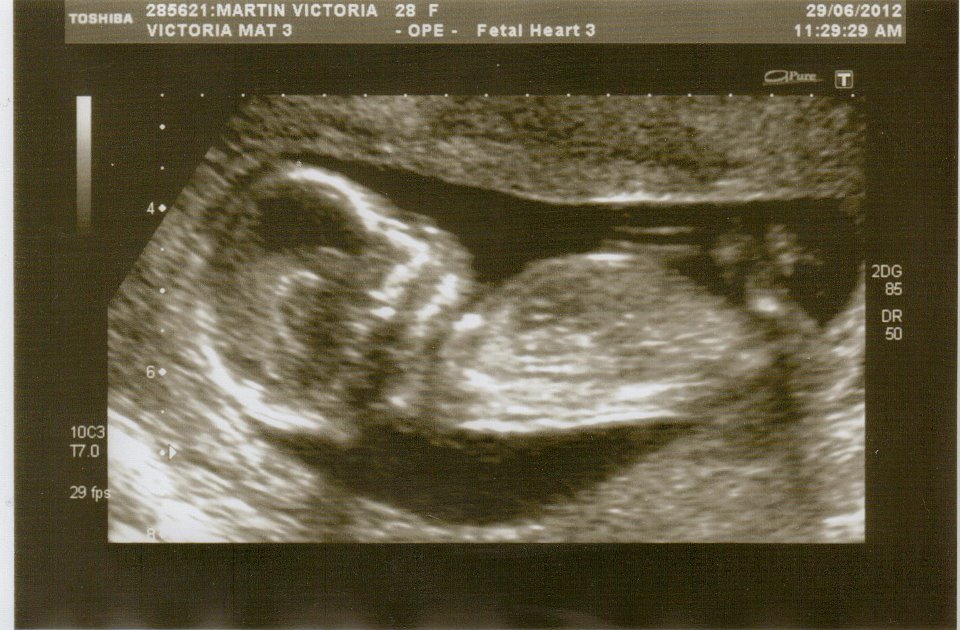

I myself have no idea as im not very good at guessing by ultrasound but was wondering if anyone has any idea as to what gender my baby might be? xxx

looks like there is a upward pointing tip of the nub to me....just look just above the thigh......also the head and face look very boyush....:)...as soon as i looked at it i thought boy too....if that is to mean anything.....but i can def see a tip just behind the bum above the thigh.

I say boy 💙 by skull!

I don't see any clues...look busy down there if I had to guess I lean boy for no reason whatsoever! Lol